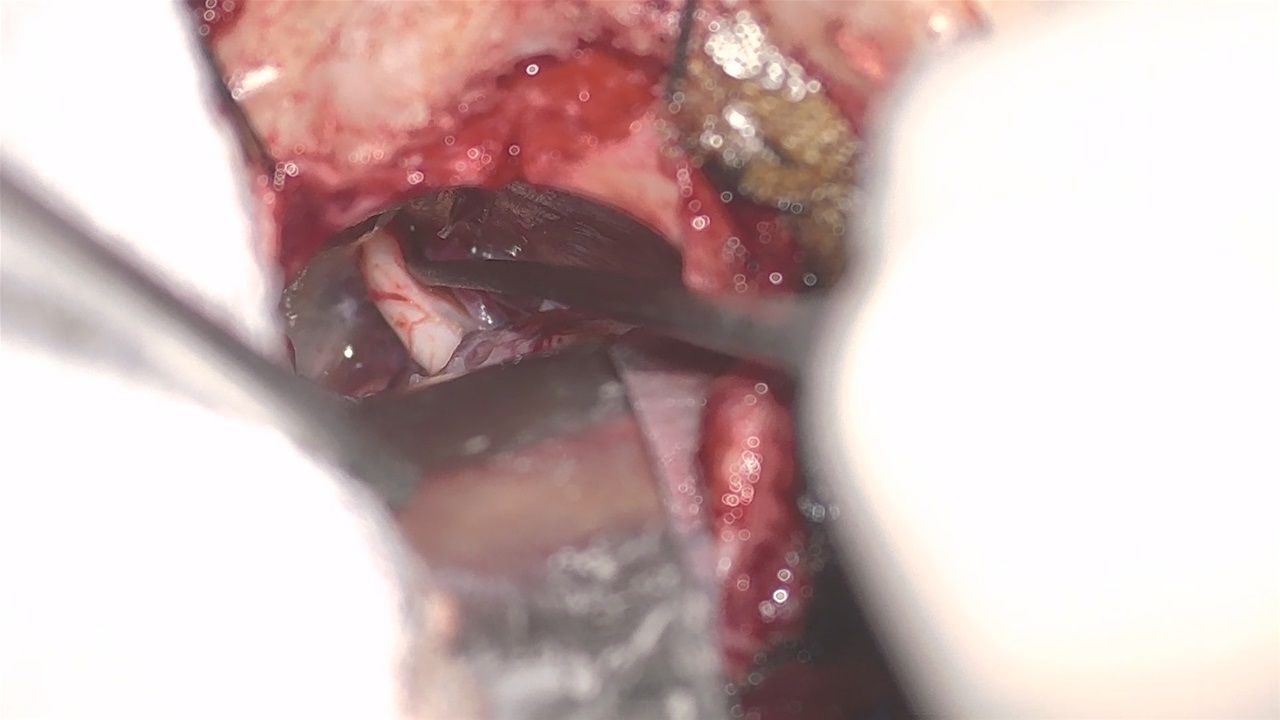

Microvascular decompression (MVD microvascular decompression)

Microvascular decompression of the trigeminal nerve is the causative and indicated method of treatment in younger individuals. With a 2 cm lateral hyponeurotomy, the trigeminal nerve is separated from a vessel that presses on it (usually the superior cerebellar artery) and a special material (Teflon) is placed between them to prevent contact. The improvement in pain is immediate and usually lasts for life. The operation takes about 2 hours and is performed under general anaesthesia.

Microvascular trigeminal decompression, with the superior cerebellar artery pressing on the nerve.

Removal of the artery from the trigeminal artery.

Placement of teflon between the trigeminal artery and the artery.